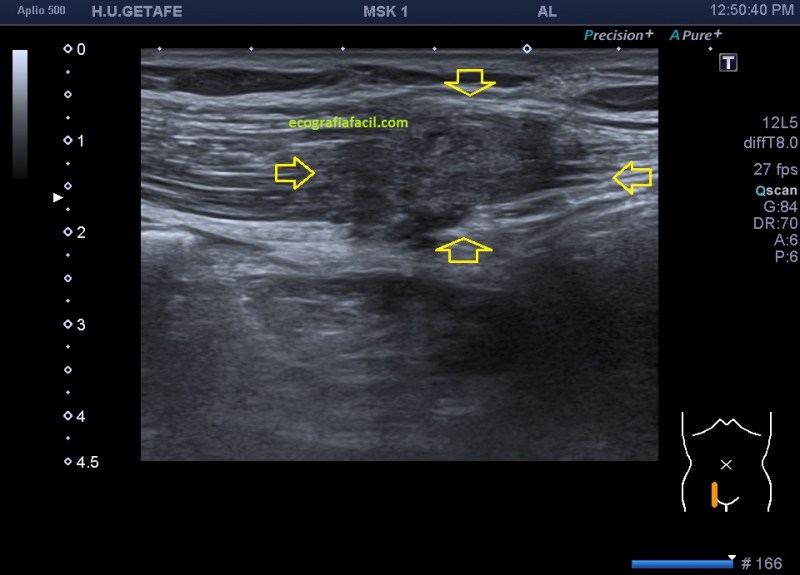

En este estudio, el estudio (perdón por la redundancia) contralateral no afectado es muy importante, diría yo, que una vez hecho el primer contacto con la lesión, lo primero es ir a comprobar la semiología del músculo y su ecoarquitectura normal. Encontramos en la zona contralateral sana un músculo de aspecto en “cielo estrellado”(punteado sobre fondo hiperecogénico) en el corte transverso y en forma de “penacho”(fibras alargadas hiperecogénicas sobre el fondo hipoecogénico de músculo) en longitudinal.

Una vez que tuve controlado el aspecto normal de músculo en la misma localización donde la paciente tenía el bulto, me dirigí a la región del bultoma y estudié la lesión, descrita con anterioridad, siguiendo el protocolo de actuación en caso de neoformaciones, control, medidas, doppler color y power y finalmente comparativa.

Semiológicamente es evidente una desestructura en el vientre muscular de recto anterior, que borra el aspecto normal del músculo y lo aumenta de tamaño aumentado su hipoecogenicidad. Los bordes son irregulares y de márgenes mal definidos.